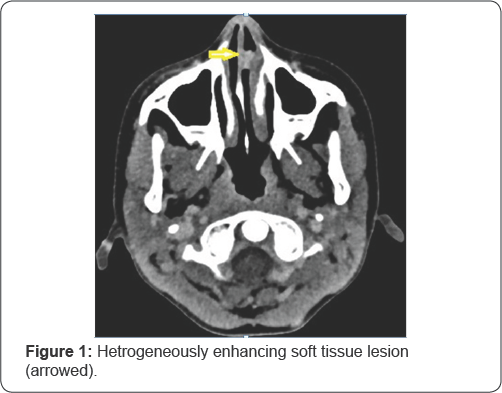

A nine year old child presented to the outpatient department of otolaryngology and head and neck surgery with 5 months history of recurrent nasal bleeding from left nasal cavity and left sided nasal obstruction. History of frequent nose picking present. On anterior rhinoscopy, single red fleshy lobulated mass of size 1.5x1.5cm was present in the left nasal cavity surrounded with blood clot. Contrast enhanced Computed tomography (CECT) of Paranasal sinus revealed a heterogeneously enhancing soft tissue lesion attached to the cartilaginous part of nasal septum (Figure 1). Rest of the head and neck and systemic examination was normal. Hence provisional diagnosis of a vascular nasal mass was made. Patient was planned for endoscopic excision under general anesthesia.

CECT of the nose and paranasal sinuses is the preferred investigation for diagnosis of vascular lesions. Magnetic Resonance Imaging (MRI) with T2 weighted images reveal vascular soft tissue lesions with multiple flow voids [8].